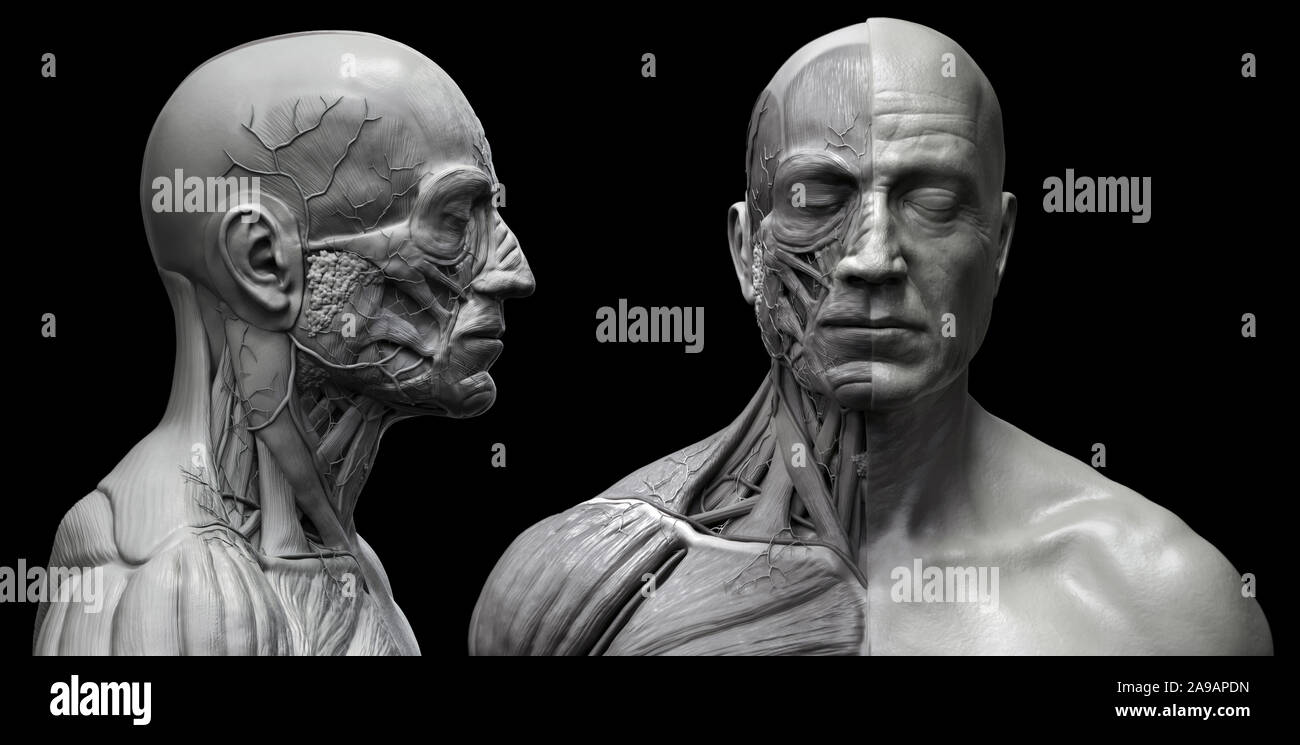

RF2A9APDN–Menschliche Körper Anatomie Muskeln Aufbau eines männlichen, Vorderansicht Seitenansicht und Perspektive, 3D-Rendering im Hintergrund